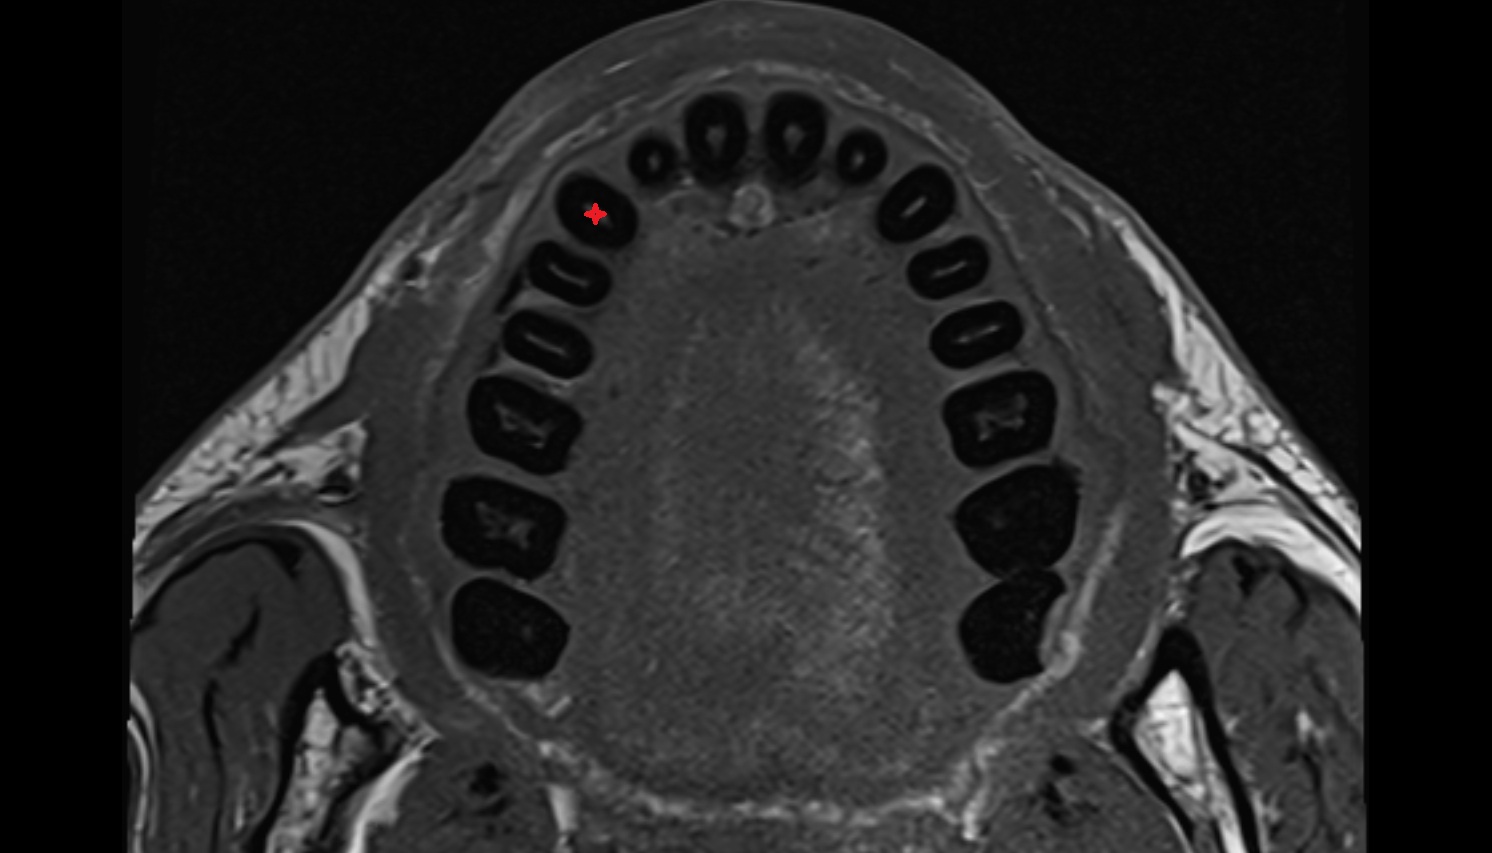

- Central inferior incisor tooth

- Central superior incisor tooth

- Inferior canine tooth

- Lateral inferior incisor tooth

- Lateral superior incisor tooth

- superior canine tooth

- Superior first molar tooth

- Superior first premolar tooth

- Superior second molar tooth

- Superior second premolar tooth

- Superior third molar tooth

- Inferior first premolar tooth

- Inferior second molar tooth

- Inferior second premolar tooth

- Inferior third molar tooth